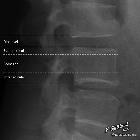

Disc protrusions are a type of disc herniation characterized by protrusion of disc content beyond the normal confines of the intervertebral disc, over a segment less than 25% of the circumference of the disc. The width of the base is wider than the largest diameter of the disc material which projects beyond the normal disc margins. The protrusion must not extend above or below the relevant vertebral endplates .

Disc bulge is distinguished from a disc protrusion in that it involves more than 25% of the circumference.

A disc extrusion is distinguished from a disc protrusion in that the base of the protruded disc material is narrower than its 'dome'. Furthermore, this material may extend above or below the disc level.